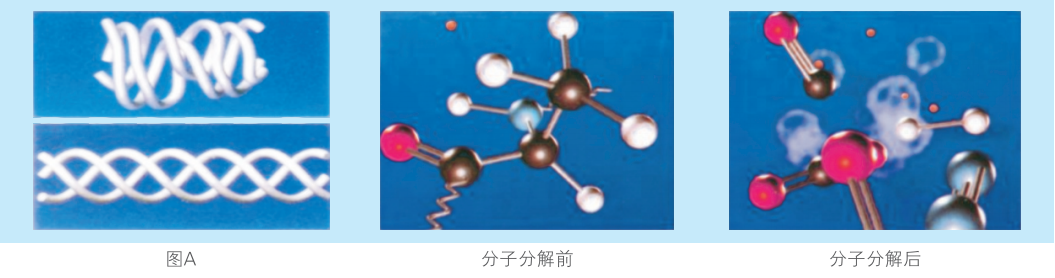

等離子手術理論

等離子體技術是一種特定波形下的電能通過多極刀頭在人體組織中激發(fā)血液、粘膜、髓核組織的膠原蛋白分子中的介質( Nacl)產生等離子體狀態(tài),再由等離子體中的高速帶電粒子直接打斷組織分子鍵,使組織蛋白汽化分解成H2、O2、CO2、N2和甲烷等低分子量氣體,達到對組織的汽化、切割、打孔、消融、皺縮、剝離、止血、修復作用。